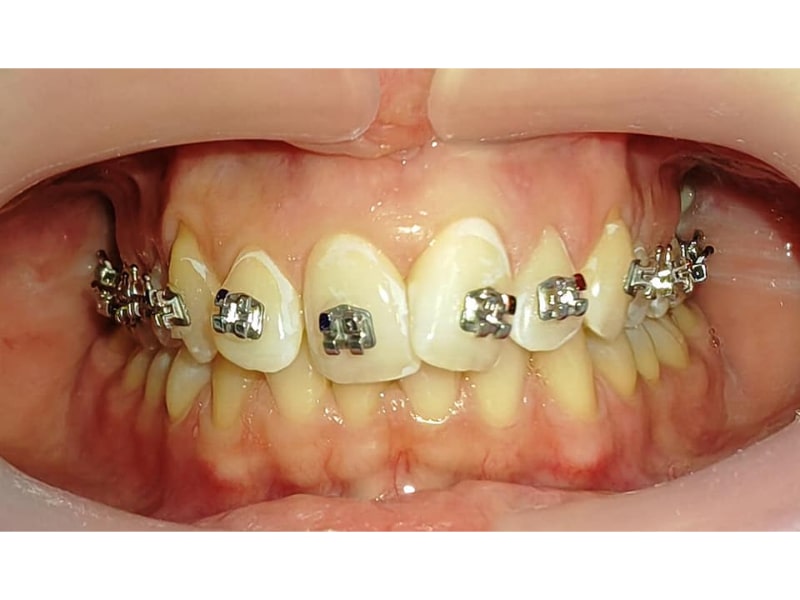

Ortodonție